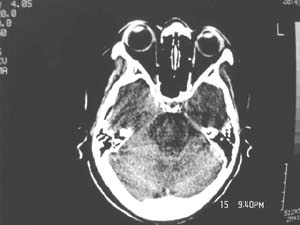

女,60岁,反复头痛3天,呕吐3小时伴昏迷10分钟入院检查。

右额叶占位,有占位效应,中线偏移,病灶位于镰旁,呈囊实性并有钙化,

考虑:1.脑膜瘤。2.胶质瘤。

理由:1.病灶位于前颅凹及镰旁,有明显占位效应---支持脑膜瘤。

2.病灶呈囊实质性并有条状钙化,符合胶质瘤改变;

另外也不排除包虫病的可能。

右额叶占位,有占位效应,中线偏移,病灶位于镰旁,呈囊实性并有钙化 kaolv  少枝胶质瘤。胶质瘤。

病变范围较大,累及左额叶,内见钙化。及高密度灶。考虑;胶母伴卒中可能大。